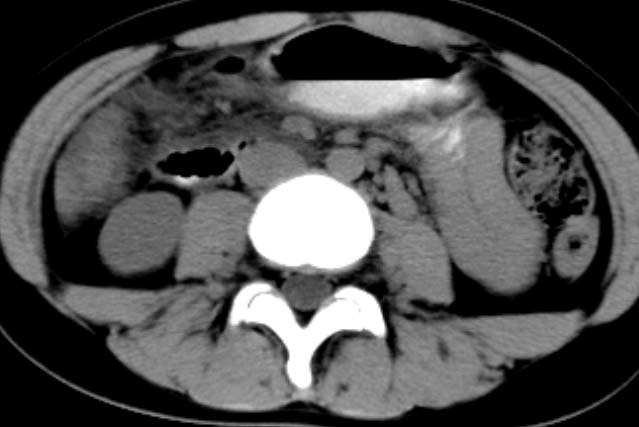

女,14岁。腹痛3天。腹部触诊未触及包块。碘剂阳性未增强。求助战友。。。。。。。。。。。

胰头部明显肿大,胰周间隙浸润,考虑胰腺炎可能性大

胰头部增大,周围模糊,有渗出,胰腺炎可能性大,建议结合化验检查;左侧输尿管上段略扩张.

胰头部明显肿大,胰头周脂肪密度加大。十二指肠环扩大受压。胰管未见确切扩张。考虑胰腺炎可能性大。建议增强扫描。

胰头部增大,周围结构模糊,并明显见渗出。支持:急性胰腺炎!

1)急性胰腺炎。2)肝右叶后上段肝内胆管结石。3)左侧输尿管上段扩张,原因待查。

胰头明显增大,周围结构不清,诊断胰腺炎的话,结合血或尿淀粉酶诊断比较明确了。

胰头部明显增大,胰管未见明显扩张,周围肠系膜血管显示清楚,胰头周围明显见渗出,还是考虑胰腺炎

胰头部明显肿大,胰周间隙浸润,胰管略增宽支持;胰腺炎诊断。

胰头明显肿大呈肿物样,周围脂肪密度增高,结合病人年龄及临床表现,首先考虑炎性改变,建议结合实验室检查明确。必要是复查或mr检查

病灶应在胰头下区,不一定是胰头,结合周边低密度水肿,是否可能为十二指肠(xi)室炎症或其它炎症。

胰周无明显渗出,吉氏筋膜未见增厚。血尿试验室检查不支持。排除胰腺炎。